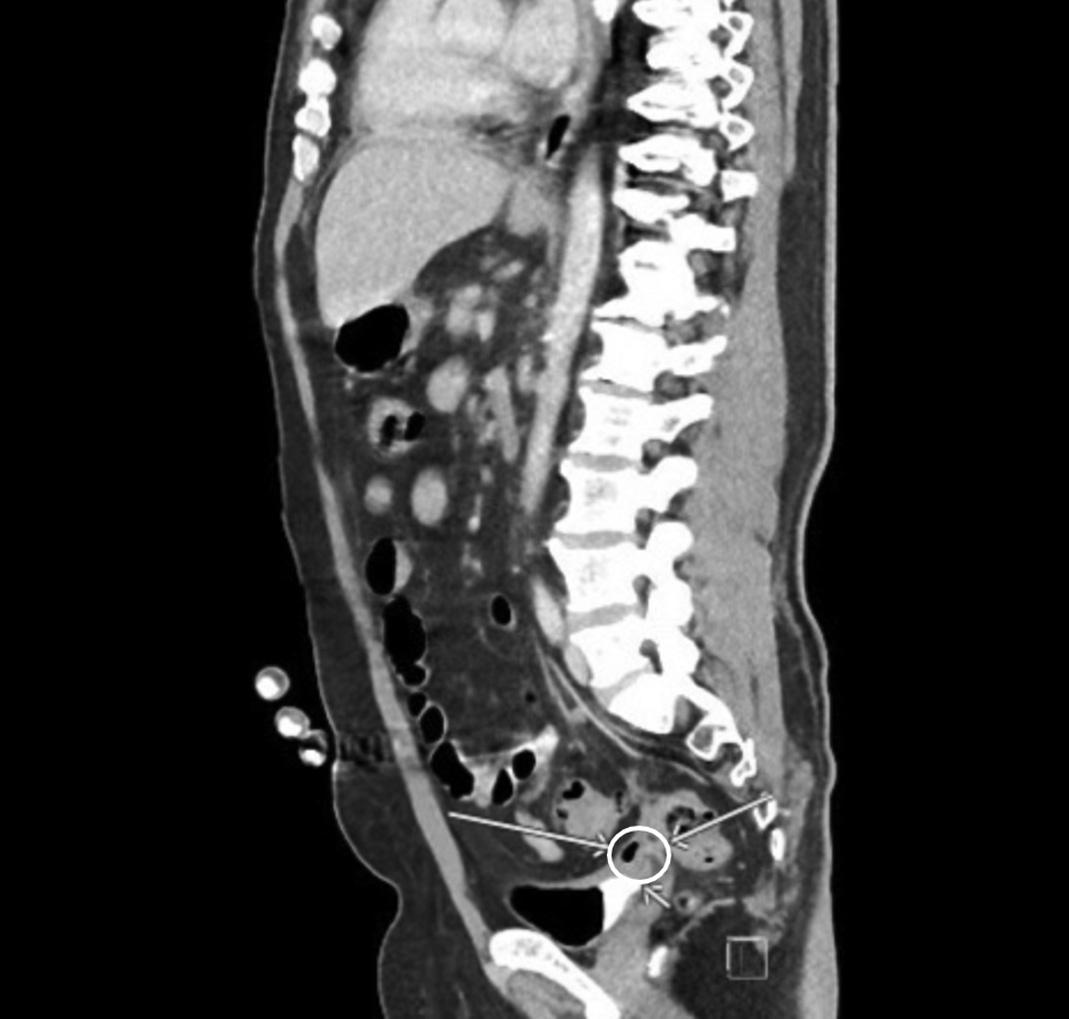

Emergentcomputedtomographyoftheabdomenand pelvisrevealedalargeleftretroperitonealandperitoneal hematomasecondarytoleftRAArupture,aswellasconcern fordevelopingsplenicinfarctsintheleftlowerrenalpole (Image).Thepatientwastakenemergentlytotheoperating room(OR)forexploratorylaparotomywithintwohoursof EDarrival.Sheunderwentsuprarenalcross-clampingwith repairoftheleftrenalarteryandligationofrenalvessels.She returnedtotheORtwodayslaterforleftnephrectomyand abdominalclosure.Shewasextubatedandtransferredtothe floor.Shewasdischargedhometwodayslaterin goodcondition.

AlthoughtheincidenceofRAAisrare,rangingfrom 0.01–0.09%ofthepopulation,thiscasereportillustratesthe importanceoftimelydiagnosis.3,4 Contemporaryrupture ratesareestimatedatapproximately3%.5 Theyaremost commonlyfoundinwomen >60yearswithriskfactors includinghypertension, fibrodysplasia,andconnectivetissue disorderscausingarterialmedialwalldegeneration.Patients notablylacktraditionalcardiovascularriskfactorssuchas cigaretteuseanddiabetes.6,7 Aneurysmsareusually asymptomaticandfoundincidentallyonscreeningimaging, althoughpatientscanpresentwithsymptomssuchas hypertension, flankpain,hematuria,andabdominalpain.5

AsthepresentationofarupturedRAAcanbeidenticalto themorecommonrupturedovariancyst,considerationof rareserioussurgicalpathologyshouldbemaintainedfor patientswithacuteabdominalpainandfree fluidonexam. Bradycardiainthesettingofhemoperitoneumisawell describedphenomenonparticularlyinrupturedectopic pregnancyandcanindicatehemorrhagicshock,bothof whichwereconsiderationsinthecasereportedhere.8,9 Other emergentcomplicationsofRAAincludethrombosis, embolism,andobstructiveuropathy.

Thisisacaseofspontaneousruptureofaleftrenalartery aneurysmasadangerousmimicofovariancystrupture. Whileovariancystruptureremainsthemostcommoncause ofspontaneoushemoperitoneuminnon-pregnantwomenof childbearingage,RAAshouldbeconsideredwith confirmationviacomputedtomography,particularlyin casesofhemodynamicinstabilitytoensureprompttreatment ofadiseasewithpotentiallyhighmorbidityandmortality.